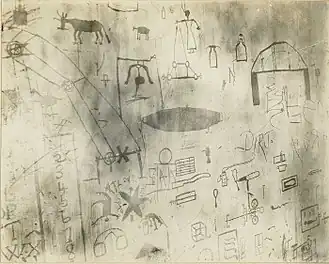

Рисунки, выцарапанные на стене пациентом с диагнозом «деменция прекокс». Из архивов госпиталя святой Елизаветы. Начало XX века, Вашингтон | |

Изначально шизофрения имела данное Эмилем Крепелином название dēmentia praecox — «раннее слабоумие»[28].